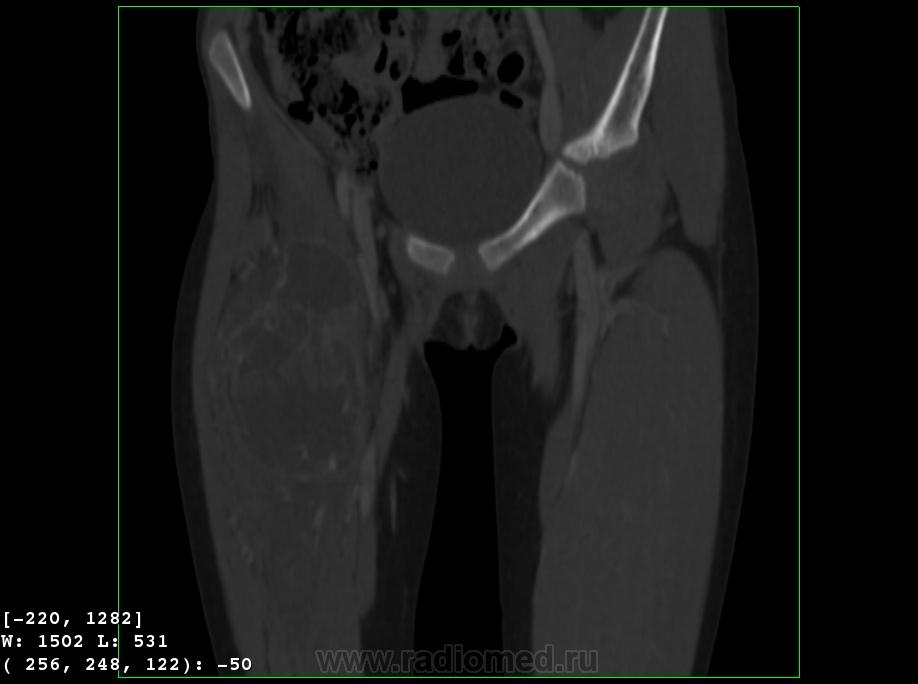

Девочка 9 лет. Родители отмечают, что 2 месяца назад девочка начала предъявлять жалобы на боли в правой пятке. Обследовались, патологии в стопе не нашли. Ребёнок постепенно начал хромать. А несколько дней назад обнаружили припухлость в в/3 бедра. Болей в бедре нет, как ночных, так и дневных. Температура не повышалась. Обратились за помощью - выполнены рентгенограммы, затем - КТ.

Злокачественная опухоль - виден луковичный периостит, инвазивный рост с лизисом кости. Но какая? Вроде бы растет из костного канала. Остеосаркома? Юинг? для этих опухолей структура какая-то больно хрящевая, мягкотканная. Хондросаркома? В таком возрасте? Почему нет клиники злокачественной опухоли кости, прежде всего - болей?

Согласна. Только периостит не луковичный, четкий лизис с козырьками Кодмена-явный признак злокачественности. А насчет болей, действительно в жизни всякое бывает, но, думаю, что ребенок не может отличить их от болей в пятке (!), а прихрамывание может быть и следствием щажения конечности.

Коллеги, давайте правильно применять термины. Периостит - окончание воспаления, применяется при остеомиелите. При опухоли - периостоз - окончание избытка, продуктивного процесса. Здесь есть "козырек Кодмена", спикулообразный периостоз, но есть так же луковичный (слоистый) периостоз, который хорошо виден на отдельных КТ-срезах. Другое дело, что для диф. диагноза опухоли (то что процесс агрессивный - сомнений не вызывыает) это, по большому счету, ничего не дает. Однако, обратите внимание на вздутие. Считаю возможны варианты телеангиоэктатической или гигантоклеточной остеосаркомы. Так же не считаю возможным исключить саркому Юинга.

Да, рентгенкартина неоднозначна, конечно, в первую очередь надо исключать зло (Юинга, остеогенную), но не уверена на 100%, что это они, спикул нет, есть луковичный периостит ниже основного очага, но это не критерий злокачественности, вздутие. Был бы возраст помладше, в первую очередь подумала бы о гистиоцитозе или туберкулезе. Еще мысли об аневризмальной кисте и ГКО. Очень хочется узнать результаты гистологии.